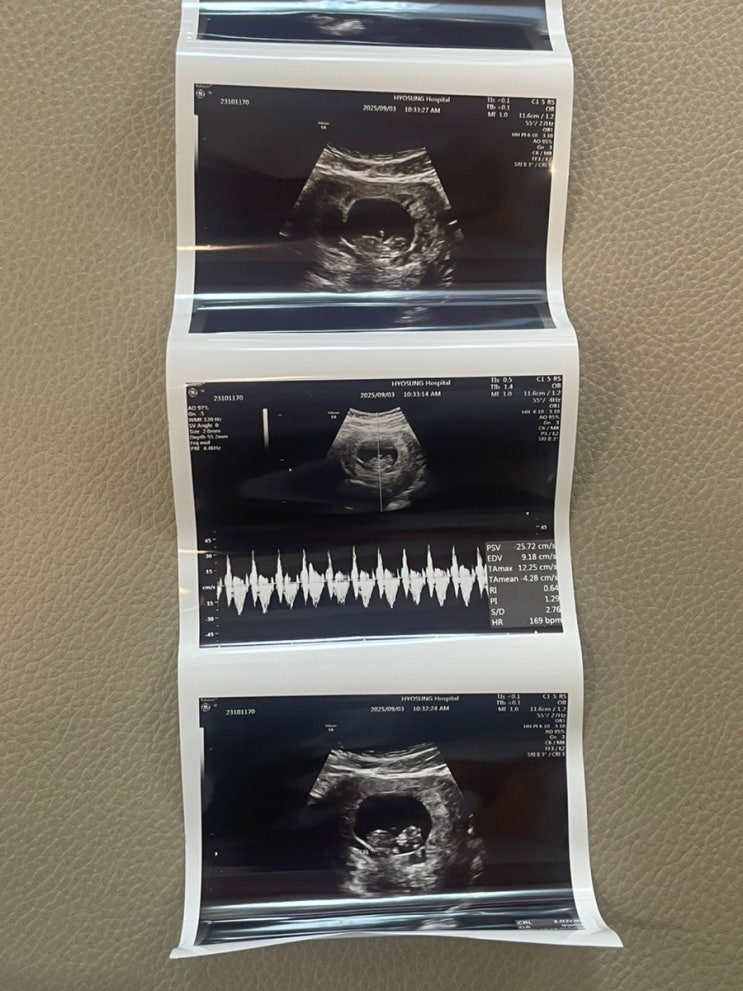

[대구 효성병원] 6주차 심장소리 확인, 7주차 쌍둥이 소실

엄청난 입덧으로 하루하루를 어떻게 보냈는지 모르겠음.. 요키는 친정집에서 데려와서 계속 신경도 못 써주...

[대구 효성 난임센터] 9주차 난임병원 졸업/ 10주차 효성 산부인과 진료

쌍둥이 한 명 보내고 그 이후로 한참 뒤 병원 가는 거라 다른 한 아이는 괜찮은지 너무 걱정이 많은 상태로...